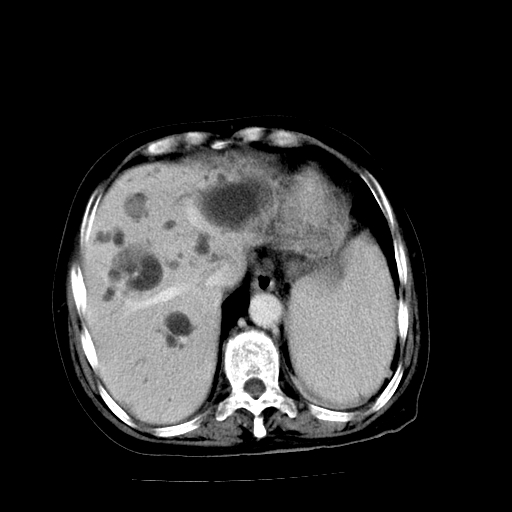

以下是引用卜一在2009-4-7 5:06:00的发言:[br]左右肝内胆管结石伴扩张合并胆系感染;不除外胆管细胞癌可能。支持! [br] [br]

以下是引用随光逐影在2009-4-7 8:21:00的发言:[br]肝内外胆管多发性结石并肝内外胆管扩张;胆系感染。